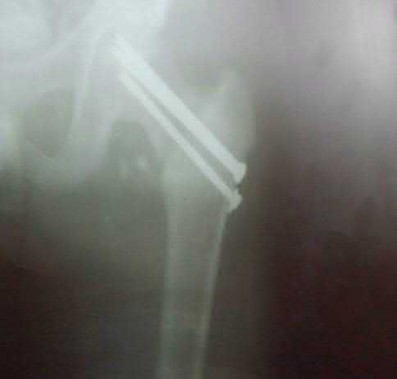

Question 1

A 12-year-old obese boy presents with vague left thigh and knee pain. He is diagnosed with a Slipped Capital Femoral Epiphysis (SCFE) as seen in similar clinical scenarios.

During percutaneous in-situ fixation, unrecognized penetration of the guide wire into the hip joint occurs. What is the most likely specific complication resulting from this technical error?

Explanation

Chondrolysis is a severe complication of SCFE characterized by rapid destruction of the articular cartilage. While it can occur idiopathically, its most established iatrogenic cause is unrecognized intra-articular hardware penetration. The 'approach-withdraw' fluoroscopic technique is required during pinning to assure pins are entirely intraosseous. Avascular necrosis (AVN) is usually due to damage to the epiphyseal blood supply (retinacular vessels) secondary to the initial displacement, forceful closed reduction, or posterosuperior pin placement.